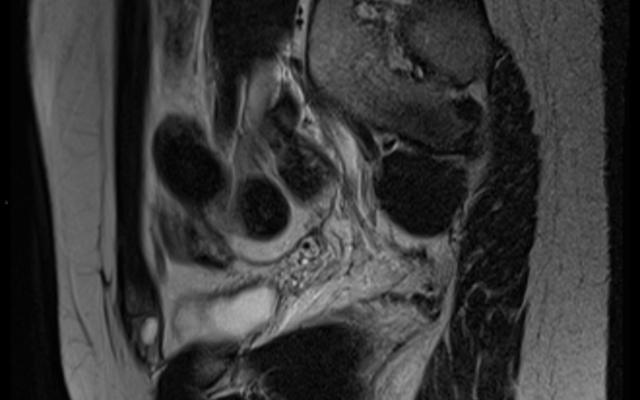

De cyste van Nuck is een zwelling in het lieskanaal die berust op een hydrocele van het ligamentum teres uteri. Deze afwijking is een gevolg van het niet of gedeeltelijk oblitereren van de processus vaginalis tijdens de foetale ontwikkeling.

Een 44-jarige vrouw had al 4 jaar last van een pijnlijke zwelling in de rechter lies. Uitgebreid beeldvormend onderzoek en meerdere puncties van de veronderstelde cyste hadden geen blijvend resultaat. Uiteindelijk werd de zwelling herkend als een cyste van Nuck, wat bevestigd werd bij operatieve exploratie. Na de operatie was patiënte verlost van haar klachten.

De cyste van Nuck is een klinische diagnose. Beeldvormend onderzoek van de zwelling kan een misleidende uitslag geven en daarmee het instellen van de behandeling vertragen.